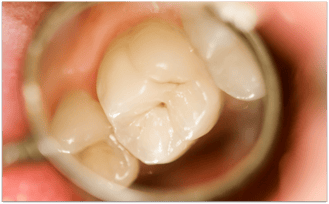

Karies in einer Fissur

Fissurenkaries an einem Backenzahn (© Zsolt Bota Finna - Fotolia.com)

Sogenannte Fissurenkaries an einem Backenzahn (brauner Punkt in der Mitte des Zahnes). Wenn diese Karies nicht behandelt wird, wird sie allmählich größer und zerstört langfristig den Zahn.